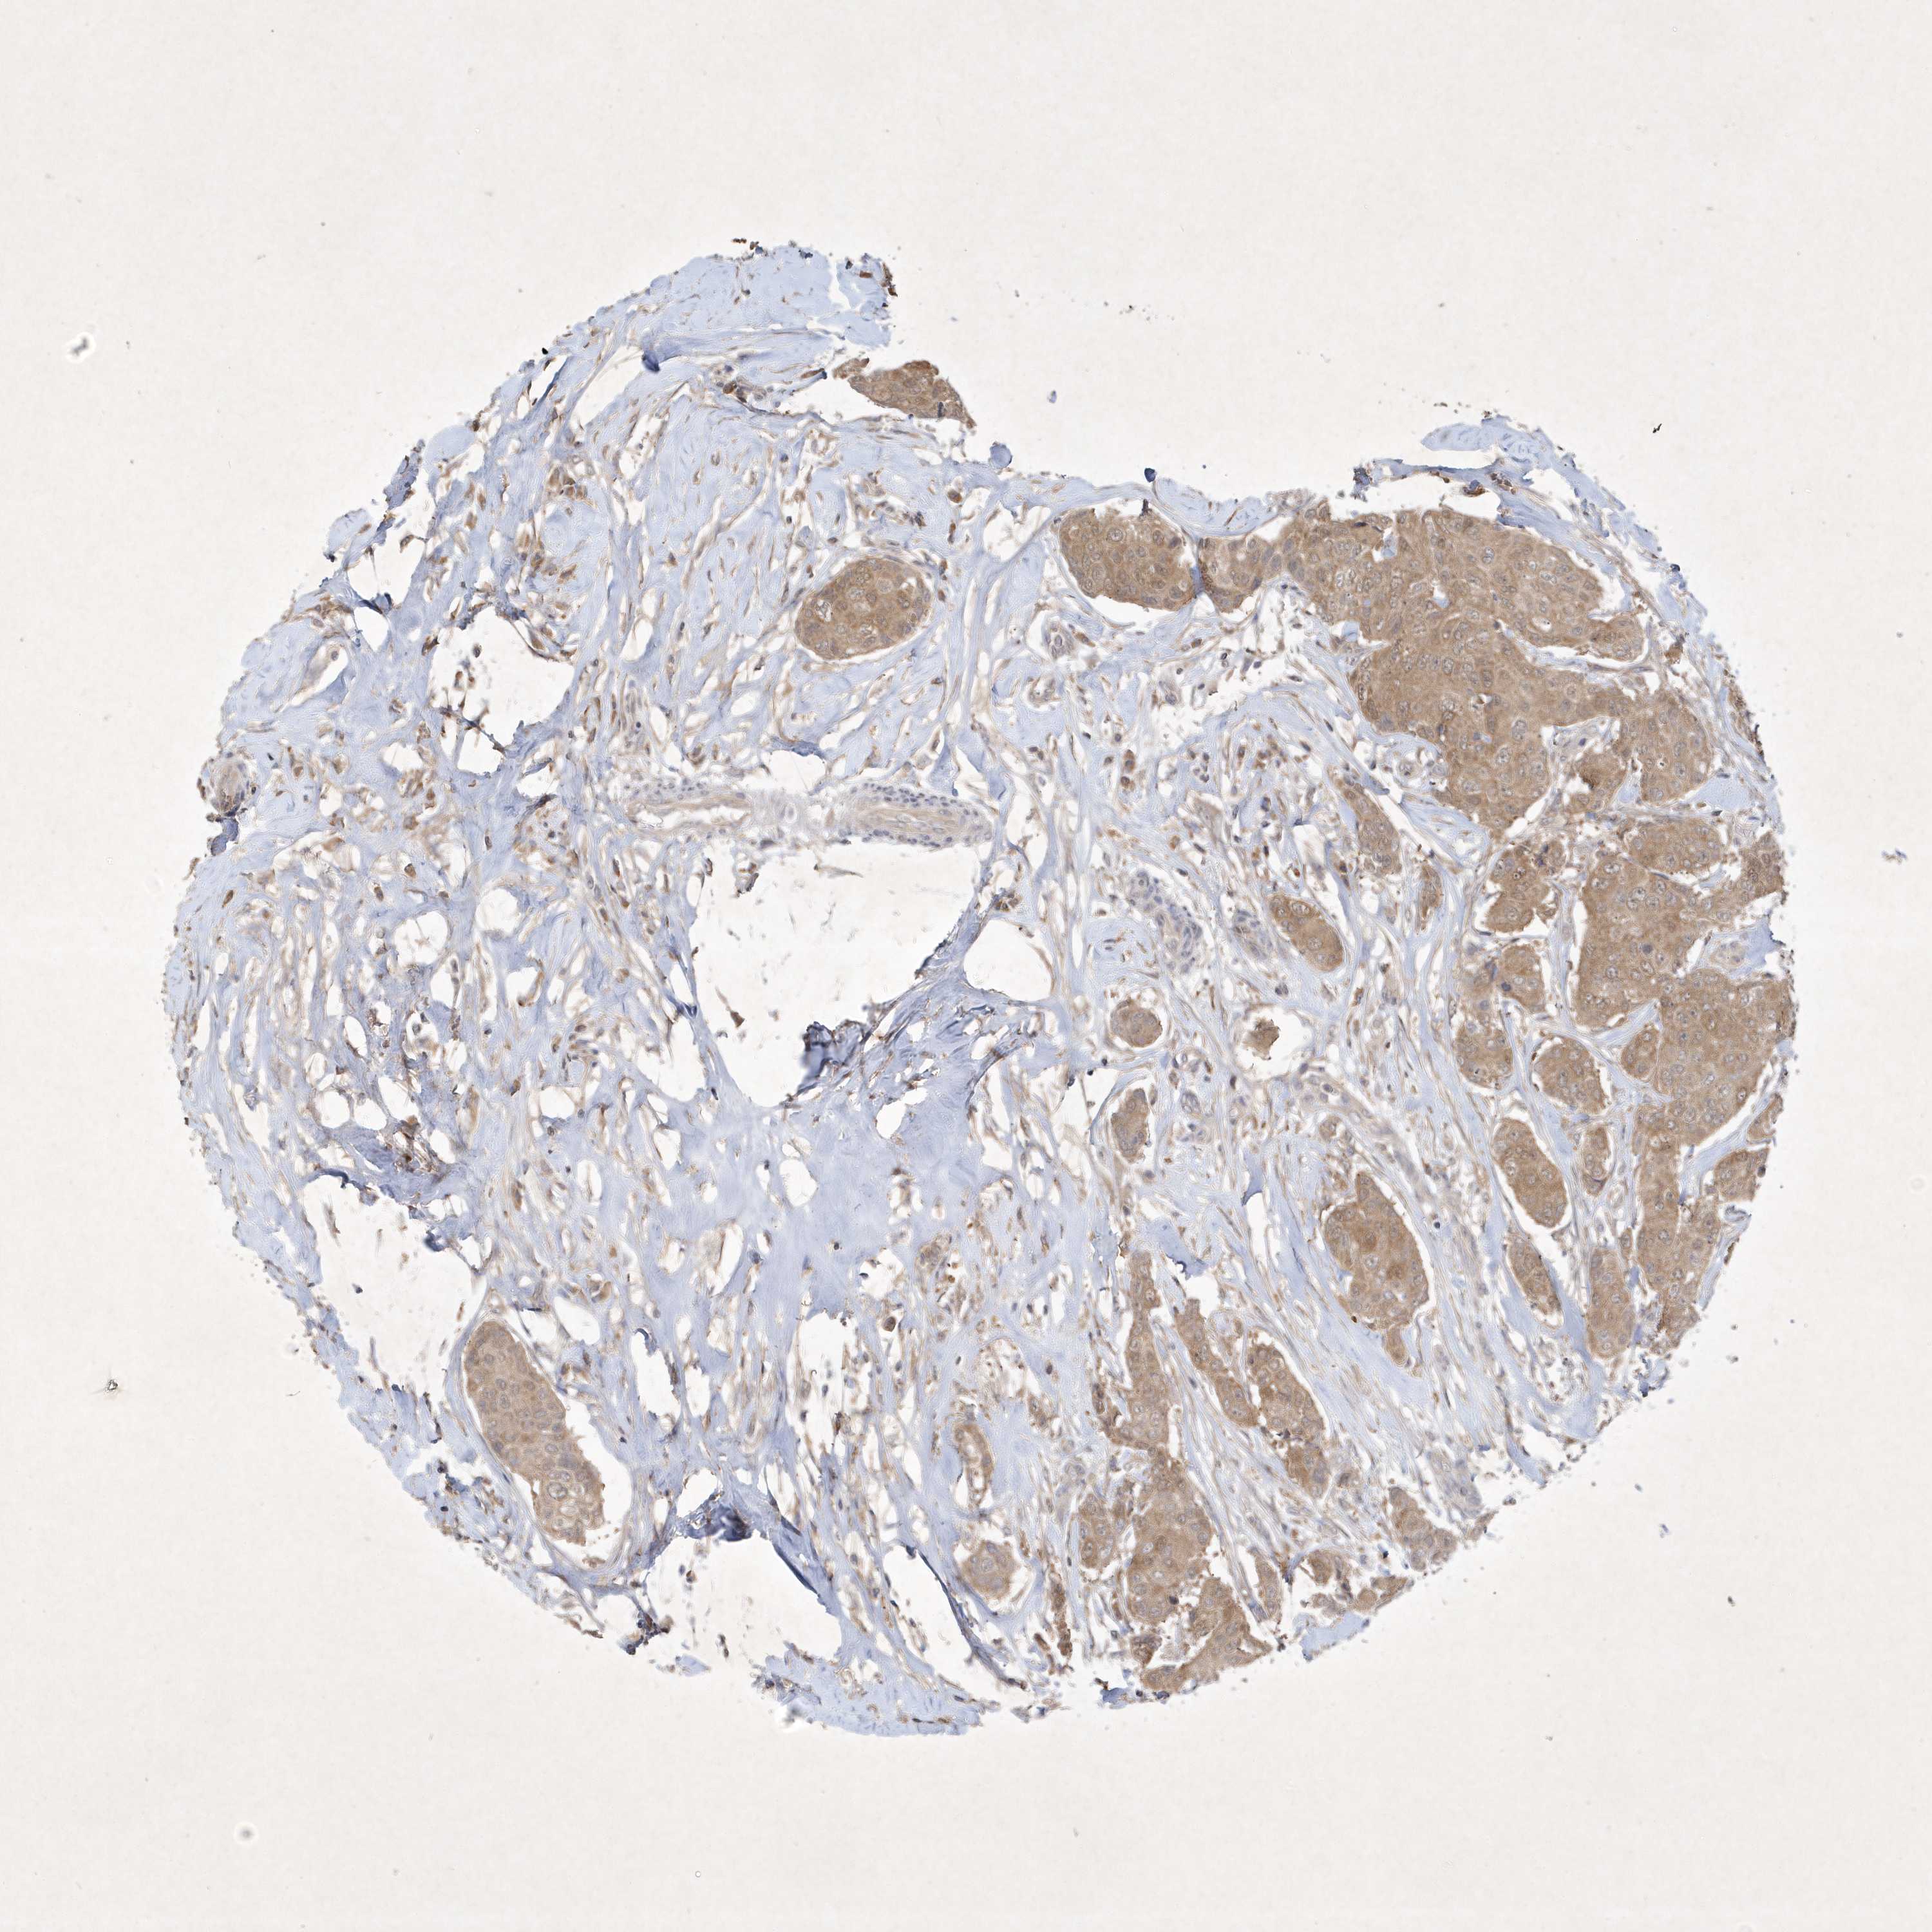

BRCA TCGA BRCA VALIDATION PROTEIN EXPRESSION